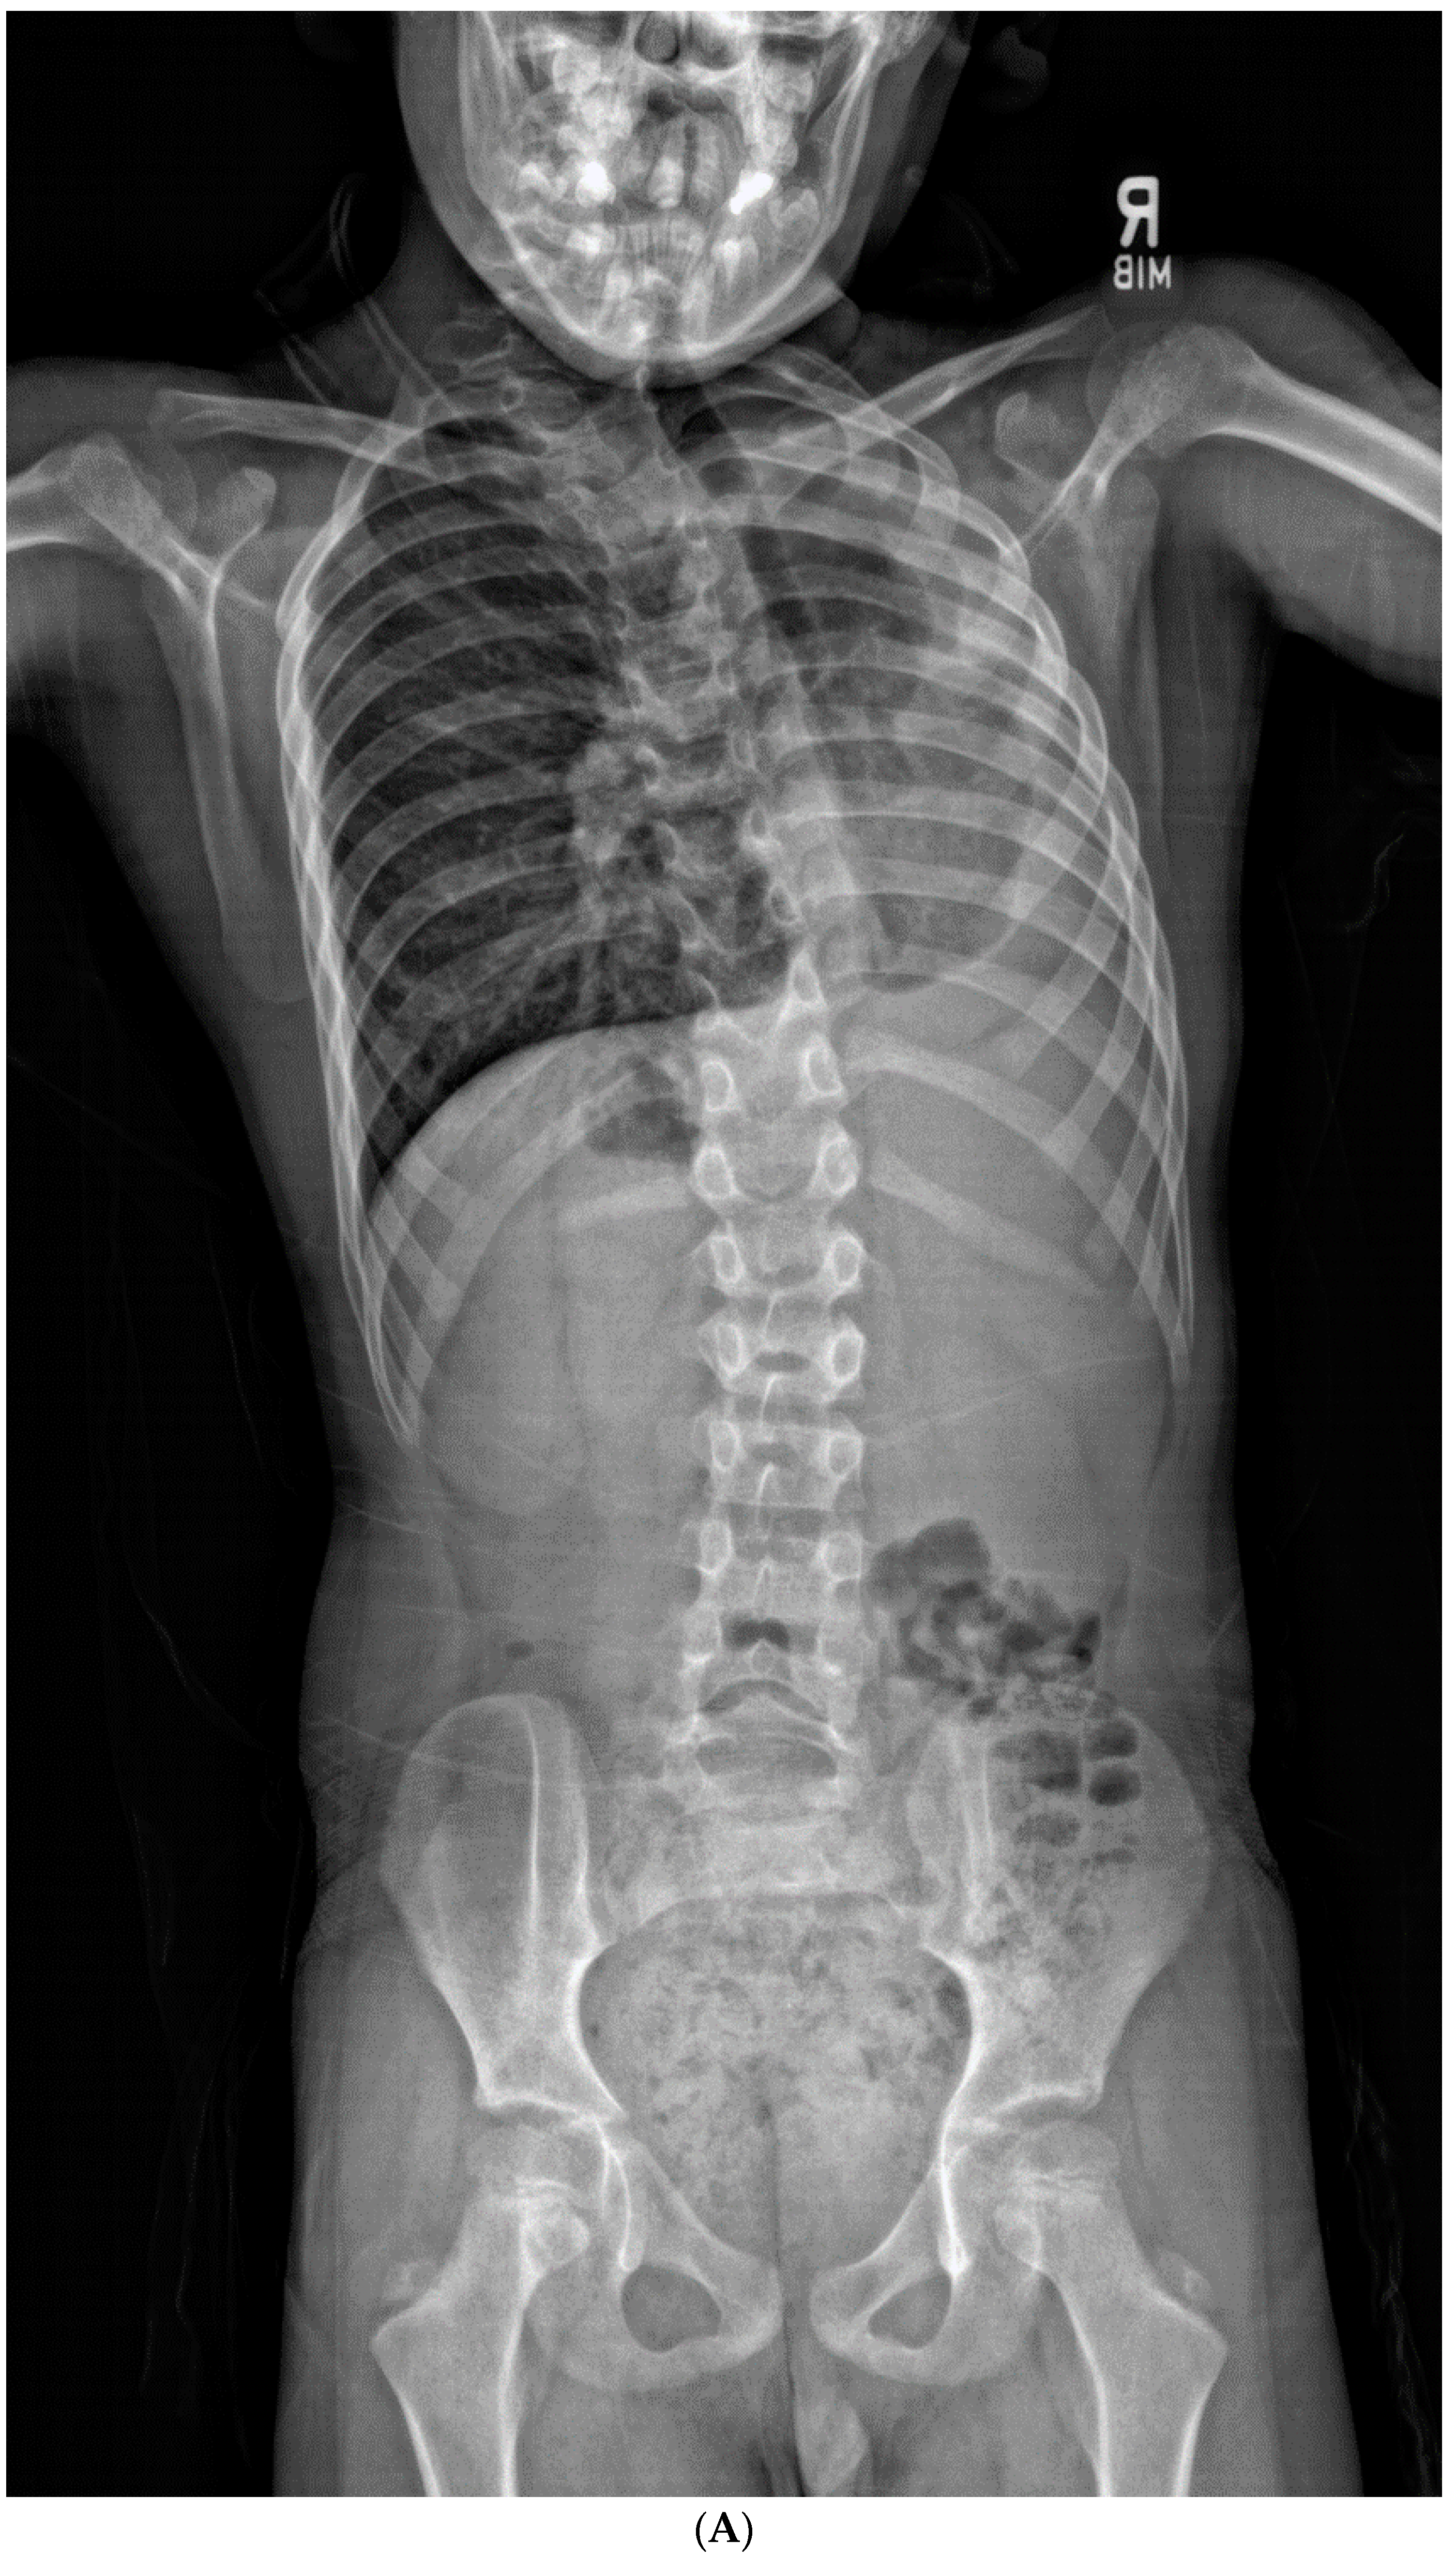

Patients in the “progression” cohort presented with a significantly larger T1S compared to the “no progression” cohort (32.4° ± 14.0° vs. 23.8 ± 7.1°, respectively; p = 0.041, effect size = 0.78). Individual patients with T1S ≥ 25° were found to be 4.62 times more likely to undergo progression than those who did not (Figure 5A–D and Figure 6A–D). Although these findings mostly trended toward significance, patients in the “progression” cohort also had lower C2-SVA (20.8° ± 30.7° vs. 57.5° ± 41.1°, p = 0.053), small thoracic curves (33.2° ± 20.6° vs. 54.1° ± 22.6°, p = 0.063), greater LL (59.3° ± 13.2° vs. 45.3° ± 12.1°, p = 0.056), and smaller interval change in C2-CSVL (−4.9° ± 21.8° vs. 18.4° ± 23.1°, p = 0.069).

Figure 5.

(A,B) Initial PA and lateral radiograph of a 7-year-old child with a 19° cervicothoracic scoliosis and T1 slope of 31°. (C,D) Follow-up PA and lateral radiographs showing progression of the curve to 38° over 8 years.

Figure 6.

(A,B) Initial PA and lateral radiograph of a 2-year-old child presenting with 17° of scoliosis at the cervicothoracic junction and T1 slope of 11°. (C,D) Follow-up radiographs showing a stable curve approximating 18° 4 years later.